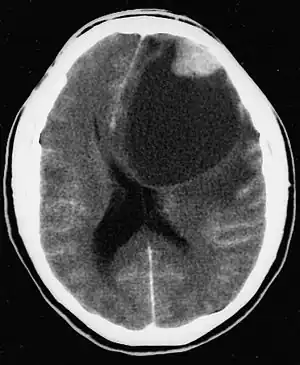

| CT scan of a brain with pleomorphic xanthoastrocytoma. The classic radiographic appearance is one of a superficially situated tumor, here a mural nodule, associated with an underlying cyst. | |

Pleomorphic xanthoastrocytoma (WHO grade II); Pleomorphic xanthoastrocytoma represents a distinctive glioma subtype -